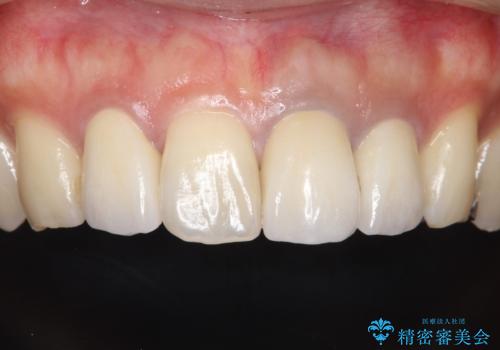

歯並びを含めて前歯をきれいにしたい インビザラインとセラミック治療

インビザラインにて歯並びを整え、上顎の前歯にセラミックを装着する計画としました。

セラミックと矯正を組み合わせることにより、審美的にも機能的にも改善することができました。